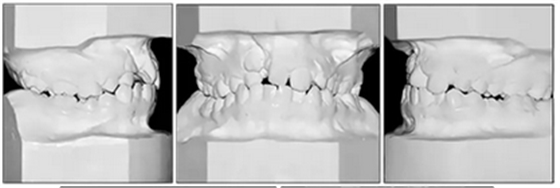

咬合關(guān)系:右側(cè)磨牙有II類關(guān)系傾向,尖牙關(guān)系II類;左側(cè)磨牙關(guān)系完全I(xiàn)I類,尖牙關(guān)系I類。上頜雙側(cè)反合,中線稍有偏離。覆合、覆蓋減少。上頜中切牙向腭裂側(cè)旋轉(zhuǎn),上頜右側(cè)尖牙頰側(cè)異位萌出,雙側(cè)乳尖牙仍存在?;颊呱项M弓嚴(yán)重?fù)頂D(擁擠度約10mm),下頜弓輕度擁擠4mm(擁擠度約4mm)(圖1 ;圖2)。牙周檢查良好。

頭部側(cè)位片測(cè)量顯示骨性I類錯(cuò)合畸形(ANB,3.5°),垂直生長(zhǎng)模式(SN / GoMe,39°),上頜中切牙后傾(1 / SN,94°)和下頜中切牙前傾(IMPA,100 °)(圖3)。